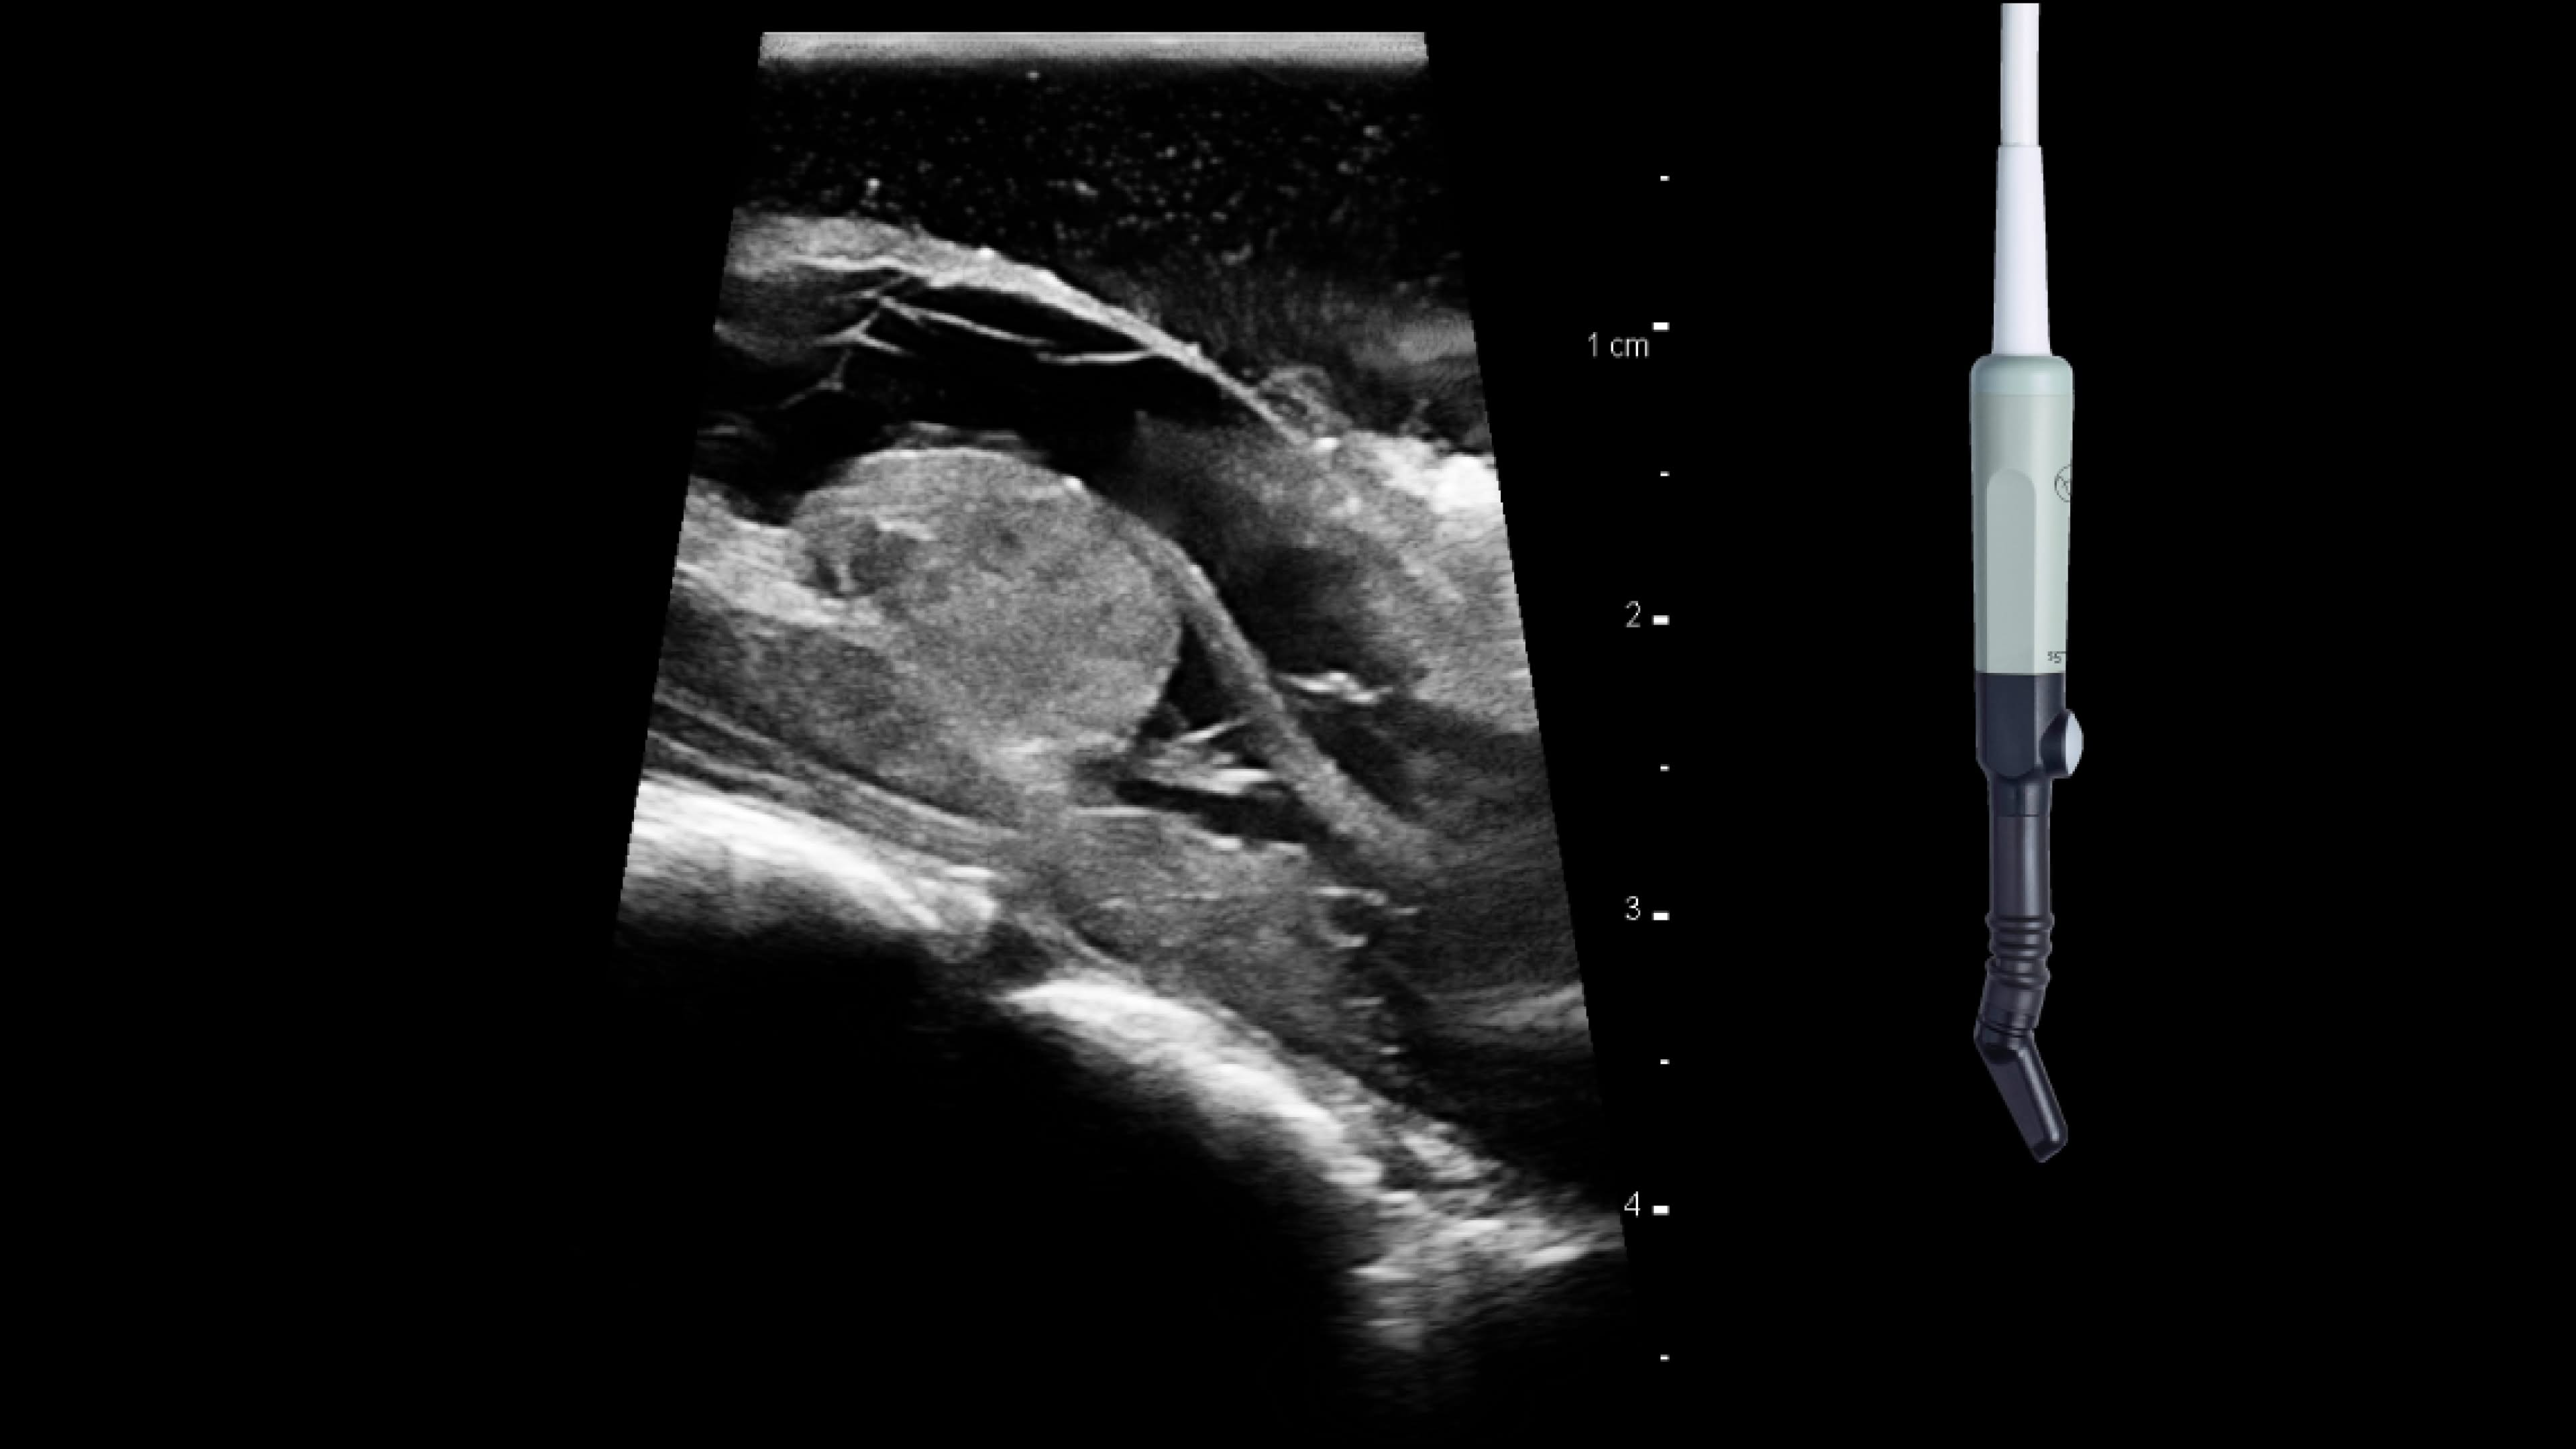

Pediatrics

Use intraoperative ultrasound during surgery to: guide safe, quick shunt placements, target the ventricle and confirm catheter placement in ventricle, reduce medical imaging hazards such as ionizing radiation and assess for brain shift and residual tumor.